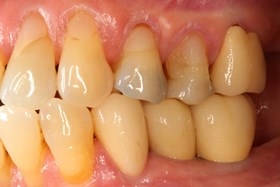

術前缺牙無法咀嚼

因植牙恢復正常咬合